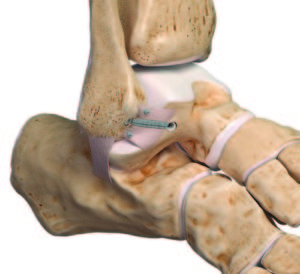

Operative Therapie

Die operative Therapie ist nur selten notwendig. Zu diesen seltenen Fällen zählen chronische Instabilitäten, einklemmendes Narbengewebe oder Verletzungen der Syndesmose. Diese membranartige Verbindung zwischen Schien- und Wadenbein besteht aus zwei Anteilen.. Sollten beide Anteile verletzt sein, ist die Naht sowie die kurzzeitige Fixierung mit einer Schraube oder einem Zugfaden nötig. Bei chronischen Instabiltäten können sowohl körpereigene Sehnen als auch Rekonstruktionen und Stabilisierungen mit speziell verstärkten Fäden vorgenommen werden. Wir kombinieren diese Stabilisierungsoperationen immer mit einer Sprunggelenksspiegelung. Bei diesem arthrokopischen Verfahren lassen sich die Verletzten Strukturen im Gelenk gewebeschonend darstellen und wir können störendes Narbengewebe entfernen.

Nachbehandlung

Nach einer operativen Therapie erfolgt eine Ruhigstellung für ca. 6 Wochen in einem speziellen Schuh/Stiefel. Meist ist eine Teilbelastung notwendig. Das Wiedererlangen der allgemeinen und körperlich/sportlichen Belastbarkeit kann 8-12 Wochen dauern, bei schweren Verletzungen auch länger.